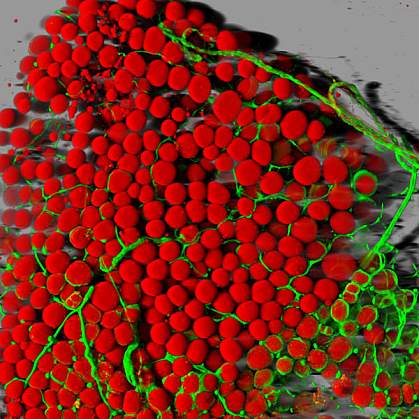

Fat tissue helps your body store excess energy. It also releases hormones and other substances that help regulate your body’s metabolism by communicating with other organs and tissues, such as your liver, pancreas, and muscles. Mammals, including people, have 2 main types of fat: white and brown. Most body fat is white fat, which stores extra energy that can then be used when needed—for example, when exercising. Whereas brown fat burns energy to help regulate body temperature.

Several cell types, including fat cells, make small pieces of genetic material, called microRNAs. The precise roles of microRNAs are currently under intense investigation. High levels of certain microRNAs have shown to correlate with the presence of several diseases, including cancer, diabetes, heart disease, and obesity.